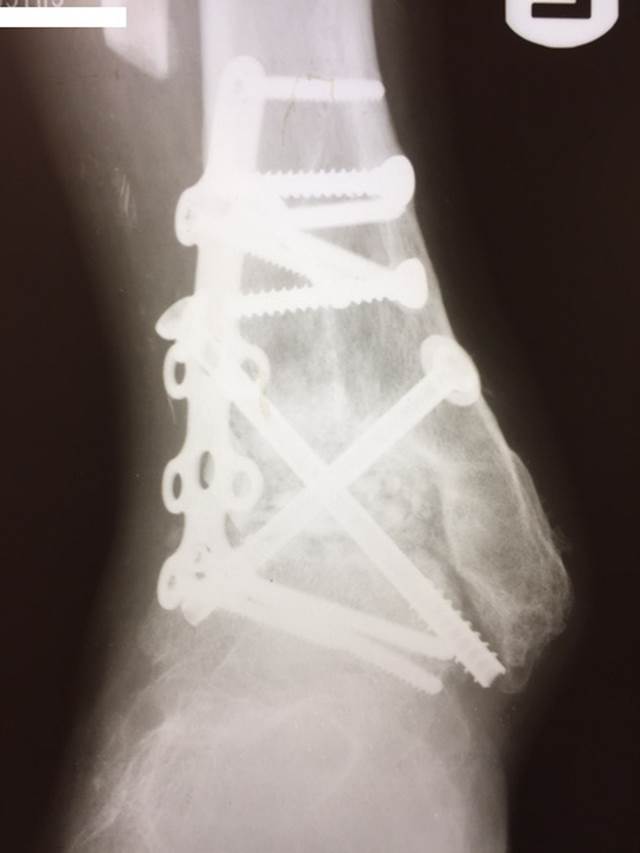

"Surgical misadventure" by another surgeon about 8 years ago. The wrong fixation was used for a flatfoot repair, & the deformity was not corrected. Patient came in with severe foot & ankle pain, with no arch at all. She was unable to play with her grandchild because the pain was so bad, & because she felt unsteady. The old hardware was removed, a lateral calcaneal lengthening osteotomy was performed along with a medial column/1st ray realignment. The ankle was painfully arthritic, & patient elected a total ankle replacement vs. an ankle fusion. She is now able to walk pain free & play with her grandchildren!